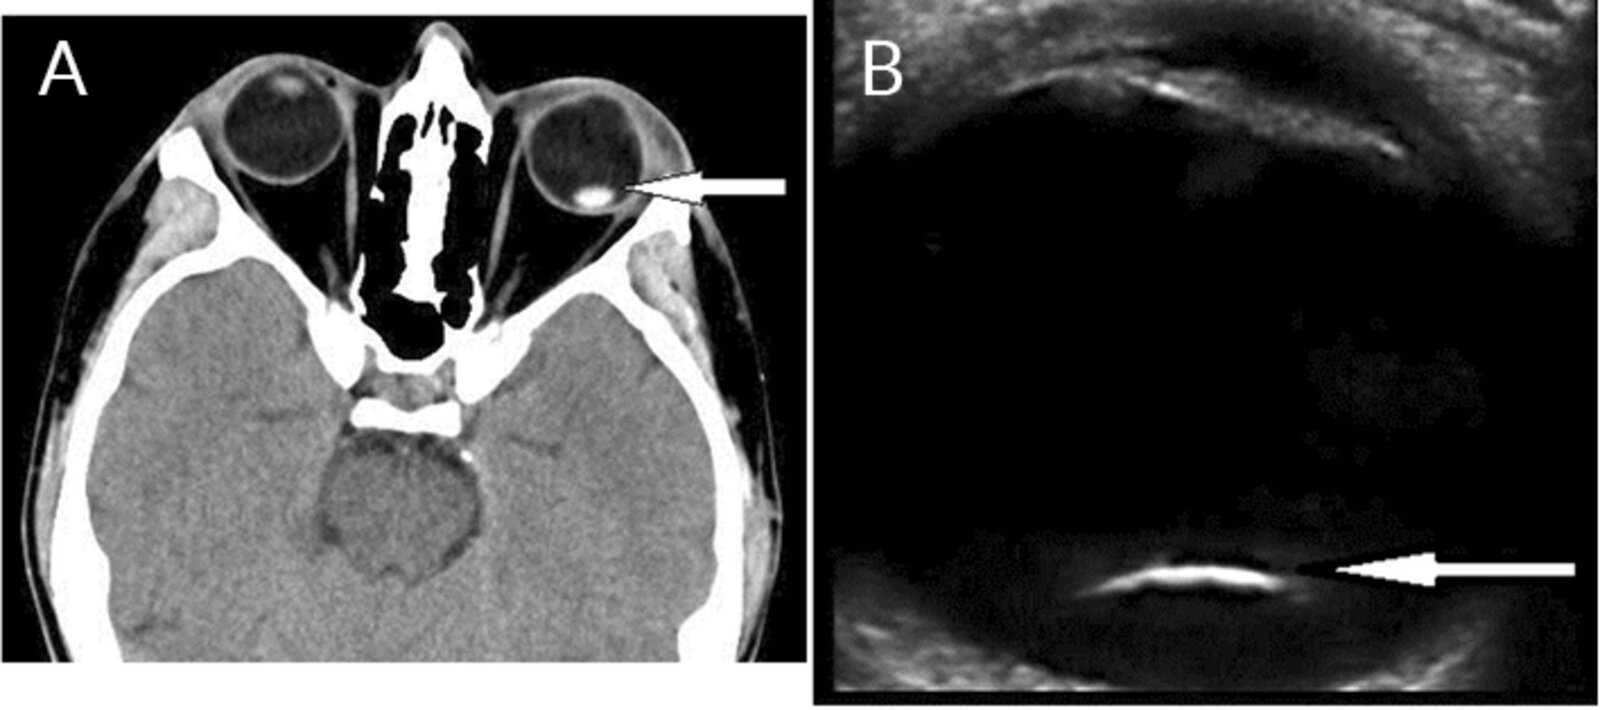

• Luxation of the lens

• Completely displaced lens; outside of the hyaloid fossa, in the anterior chamber, on the retina, or free-floating in the vitreous

• Severe visual impairment due to a change in total refractive power

• Diagnostics: visual acuity, slit lamp examination, retinoscopy, and ultrasound of the eye

• Ophthalmological assessment may include visual acuity testing, slit lamp examination, retinoscopy, ultrasound of the eye, and tonometry

• Findings include:

• The lens may dislocate into the vitreous or the anterior chamber